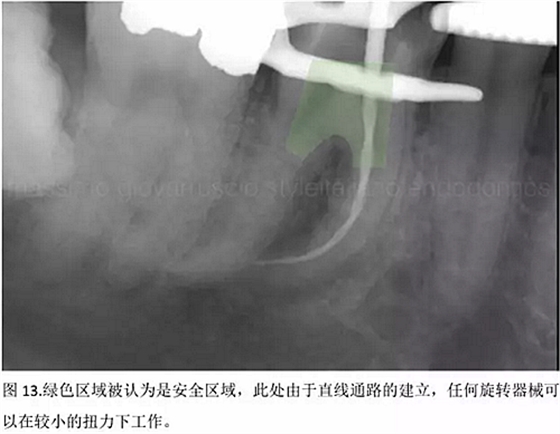

開髓后預(yù)敞、探查根管、建立直線通路是根管機(jī)械預(yù)備的第一步。在這些階段中,醫(yī)生可能會經(jīng)常遇到一些困難。這些難題包括器械折斷、臺階形成、根管歧坡或根管拉直、帶狀穿孔、根尖穿孔、根尖肘形、根尖堵塞。所有這些錯誤可導(dǎo)致根管系統(tǒng)清潔不完善從而降低牙髓治療成功率。

結(jié)論:本文的目的是描述一種旨在優(yōu)化根管根尖部分預(yù)備的預(yù)敞技術(shù)。根管頸部或冠方的早期預(yù)敞對于減少初尖銼直徑和根尖部根管直徑之間的差異至關(guān)重要。大量研究表明,手用或機(jī)用器械預(yù)敞根管能顯著減少器械折斷的發(fā)生率。下一篇文章將描述如何建立可重復(fù)的引導(dǎo)路徑。而引導(dǎo)路徑是指鎳鈦器械可沿著光滑根管壁輕易地滑行至工作長度的通路。